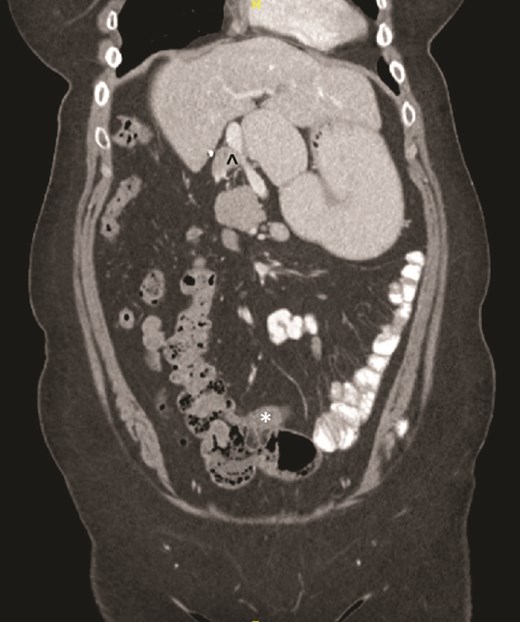

On examination, the abdomen was soft but mildly distended. Bowel sounds were heard, and the epigastrium was mildly tender. Standard bloodwork was normal. Review of an abdominal computerized tomography (CT) scan from 4 years prior showed congenital malrotation of the bowel, with the small bowel to the left of the midline and colon entirely to the right (Fig. 1). There was partial agenesis of the dorsal pancreas (Fig. 2), azygous continuation of the inferior vena cava (IVC), a retroaortic and retrocrural left renal vein, and an unremarkable spleen alongside some splenules. The PV traversed anterior to the first part of the duodenum (Fig. 3). There was relative narrowing of the distal stomach and the duodenum was nondilated.

Partial agenesis of the dorsal pancreas (*). Superior mesenteric vein (^) seen to the left of the superior mesenteric artery.